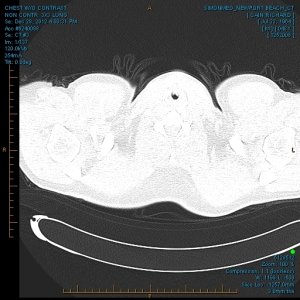

“My family and I have been the subjects of Government funded human research and/or hate crimes. These crimes are being covered-up by using the words National Security. The fact that my two minor children have the same and/or similar devices in their little bodies speaks for themselves. My sons were ages 3 and 4 when the discoveries took place. Their x-rays, blood & urine analysis present the true facts. The devices can only be introduced into the body, while being in a medical facility. All three of us were patient of the same defendant hospital.

“The CD-ROM from CCAI depicts the same images that are attached. I will bring the 01/03/2012 Simonmed Imaging CT scan which also depict foreign objets in the heart and chest.”

“Please take a look at both X-rays. Superimpose the foreign objects AKA EKG clamps and you will find that they are the same devices. when have you ever seen an EKG clamp place sideways in the abdomen? Both x-rays have been confirmed by Radiologist Louis Teresi as having foreign body reactions in the abdomen, right and left flanks.

“The obvious implant in the 2012 x-ray stands out from the others, because it at the time had not embedded into my flesh (heart).”